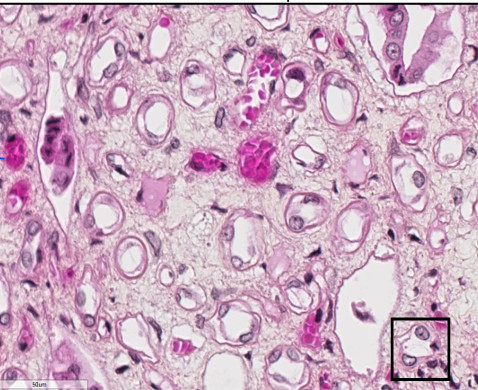

Nommez deux type d’épithélium simple dans cette image

Endothélium = autour des capillaire ( rose foncé )

Épithélium d’un tube

Qu’est ce qui est mise en évidence avec la coloration PAS dans l’image

La bordure en brosse d’un épithélium cubique

(microvillosités) est mise en évidence par la coloration PAS puisqu’elle contient des glucides, le glycocalyx